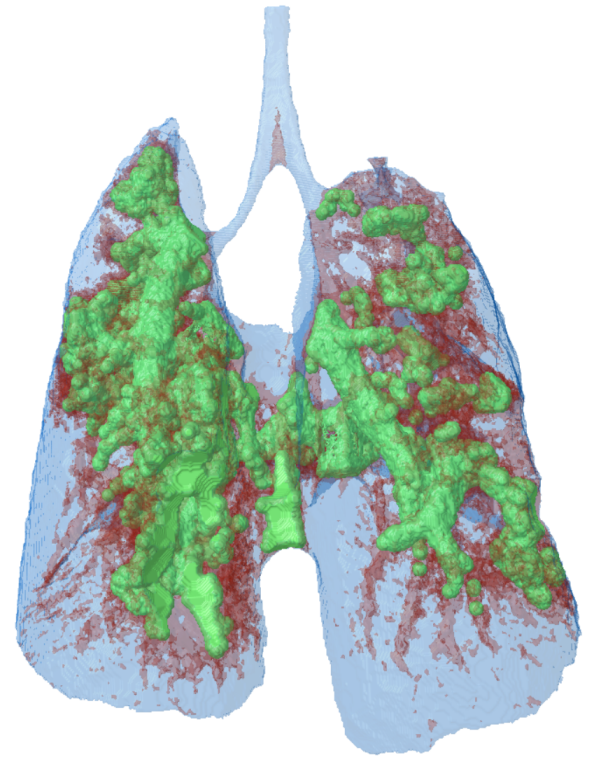

Lung tumour detection and analysis

10. 3D model of a mouse lung, made transparent to visualize thelung tumour tissue in green.